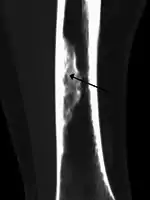

| X-ray of nonossifying fibroma of distal tibia. | |